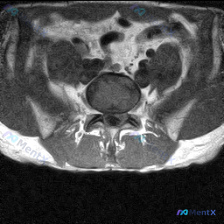

今天整理了一份只有单张腰椎MRI T2加权轴位片的椎间盘病变分析案例,跟大家分享一下读片和临床分析的思路。 病例影像基本信息 本次仅提供单张腰椎MRI T2加权轴位图像,具体读片发现如下: 1. 节段定位:根据椎体、椎弓根和关节突形态判断,该切面位于腰椎,最可能为L4/5或L5/S1水平 2. 椎间...

看到这一份腰椎MRI读片病例,临床怀疑存在椎间盘病变,我们整理一下影像资料和完整分析思路,大家一起讨论。 病例影像资料 本次提供的是腰椎MRI T2序列轴位图像,分析如下: 1. 扫描层面:位于下腰椎节段,可清晰辨认中央的硬膜囊、马尾神经根,以及侧方的关节突关节、椎旁肌肉 2. 核心影像发现: -...

这是一份单张腰椎MRI T2轴位影像的分析病例,核心问题是:临床怀疑椎间盘病变,影像上能看到什么问题?整理了完整的读片和分析思路分享给大家。 一、影像基本信息 本次提供的是腰椎MRI T2序列轴位单一层面图像,定位为腰椎椎间盘层面,我们按结构逐一读片: 1. 骨性结构与韧带:椎体形态、骨皮质连续,无...